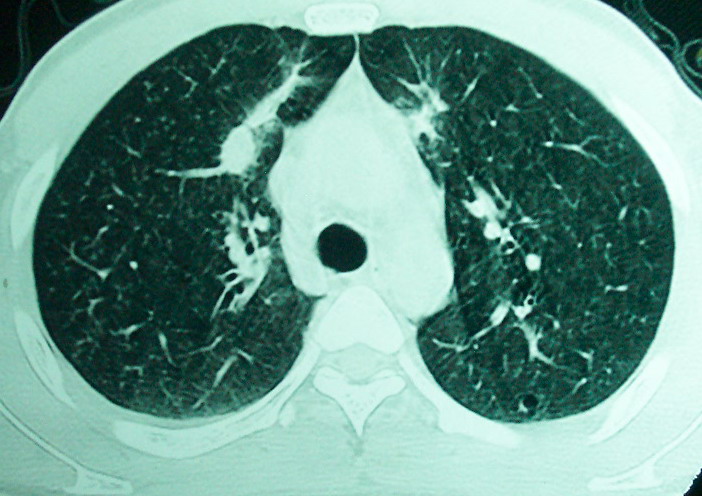

m      37y      发热   咳脓痰月余      ct肺脓肿但住院抗炎治疗后双肺内结节不知该如何解释

治疗后见左肺下野病灶较前缩小但双肺内结节影似无变化请较各位老师该如何下结论    治疗前wbc14.5 治疗后wbc 11.0

血源性肺脓肿,一般由原发感染灶引起脓毒败血症,在肺部形成小脓肿,病变变化快,容易形成肺气囊,脓气胸,主要与转移瘤鉴别,通过临床病史可分

结合临床发热,咳痰考虑为血源性肺脓肿,不过双肺结节又在肺的边缘,还是小心一点,抗炎后复查吧

血源性肺脓肿,一般由原发感染灶引起脓毒败血症,在肺部形成小脓肿,病变变化快,容易形成肺气囊,脓气胸,主要与转移瘤鉴别,继续抗炎治疗复查。

除了肺内多发结节和左肺下叶的浓疡病灶,还应注意满肺散在的小结节影,还有右上肺前段支气管内膜不光整这些细节,结合病史,肺内多发结节应考虑结核性肉芽!

如果你仔细的同层面对比,你会发现所有的病灶均有比较明显的吸收、缩小。病变的形态,特别是脓肿的形态、壁的厚薄、内壁均有很大的变化,均在往好的方面发展。与临床症状、血像均符合,治疗效果比较显著,就是肺脓肿并双肺的化脓性炎症灶。